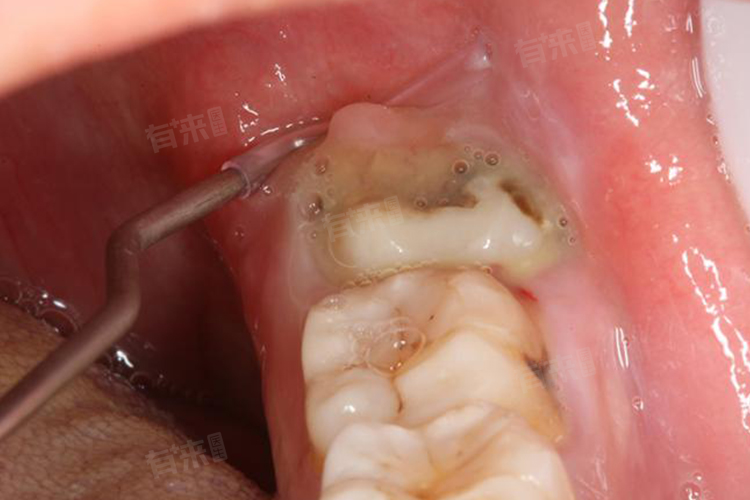

- 如果智齿是埋伏阻生齿,尤其是低位埋伏阻生,拔除时可能需要切开牙龈、去除部分牙槽骨,手术时间较长,对周围组织的创伤较大,术后疼痛、肿胀会比较明显,甚至可能出现张口受限等情况。这种情况下,通常建议休息3-7天,以便身体有足够的时间来恢复。

- 例如下颌低位阻生智齿拔除后,创口较大,术后可能会出现面部肿胀、疼痛剧烈,需要休息3-5天,肿胀才会逐渐消退,疼痛也会得到有效缓解,7天左右基本可以恢复正常生活。